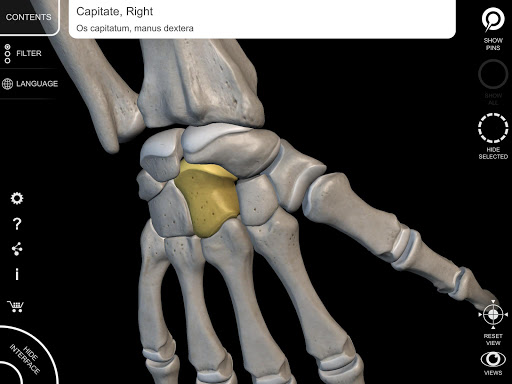

Mỗi xương của bộ xương người đã được tái tạo ở dạng 3D, bạn có thể xoay và phóng to từng mô hình và quan sát chi tiết từ mọi góc độ.

Bằng cách chọn mô hình hoặc ghim, bạn sẽ được hiển thị các thuật ngữ liên quan đến bất kỳ bộ phận giải phẫu cụ thể nào, bạn có thể chọn từ 12 ngôn ngữ và hiển thị các thuật ngữ bằng hai ngôn ngữ cùng lúc.

HÌNH GIẢI PHẪU 3D CÓ ĐỘ CHI TIẾT CAO

• Hệ thống xương

• Mô hình 3D chính xác

• Bề mặt của bộ xương có kết cấu độ phân giải cao lên đến 4K

• Ghim tương tác cho phép trực quan hóa thuật ngữ liên quan đến mọi chi tiết giải phẫu